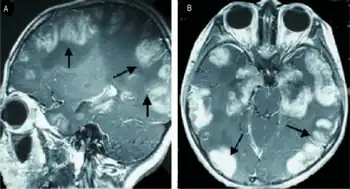

a,b)MRI scans of the brain show multiple non-homogeneous, hypodense masses along the bilateral cortex